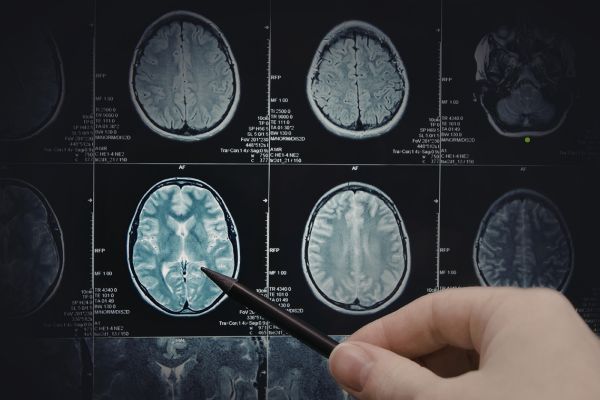

Като част от изследването, учените картографират наличието на рецептора в хипокампуса – частта от мозъка, където често започват гърчовете. Те откриват, че HCAR2 е концентриран в специфичен клетъчен тип, който вече е свързан с гърчове. Рецепторът е често срещан и в имунните клетки, наречени микроглия, които поддържат здравето на мозъка, идентифицирайки и елиминирайки заплахи като патогени, увредени клетки и натрупване на токсични протеини.